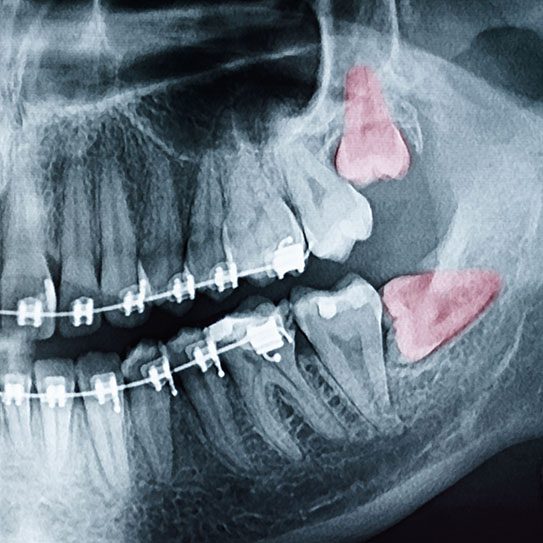

When wisdom teeth removal is recommended, your dental provider will begin with a comprehensive evaluation. X-rays will typically be used to assess the position of the teeth and surrounding structures. If removal is necessary, the procedure is usually completed by an oral surgeon under local or general anesthesia, depending on the complexity of your case.